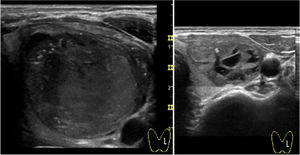

With regard to complications, reported pain during the procedure was mild in 55.2% and moderate in 23.6% of cases. Of note, virtually absent pain perception was observed in 21.2%. In all cases, this pain sensation was transient with relief within minutes. Two patients presented intranodular bleeding in one PEIT, which was self-limited with external compression and local cold application with spontaneous partial reabsorption and totally with a subsequent PEI performed two weeks after (Fig. 2). Cyst recurrence in cases treated more than once occurred from hours to a few days after each PEIT procedure (Fig. 3).